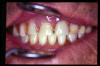

CM Caries, patología periodontal, desgaste.